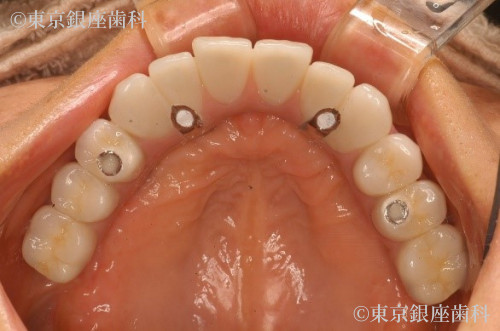

歯周病の進行により歯に動揺があり長期の保存が難しくこのままでは予後が不安であった為全顎的な治療が必要と判断。上下全ての歯を抜歯。重度の歯周病により骨が吸収されているため、上顎骨が薄く左側は上顎洞に骨を足す治療(サイナスリフト)を行い上顎に4本、下顎に4本のインプラントを埋入しワンデイインプラントを行った。現在半年メンテナンス。

抜歯即時埋入でインプラント治療を行い、その日のうちに仮歯を入れて短期間での大幅な審美、機能の回復をした。また上顎骨が薄くインプラント埋入の難しい部位には人口骨を足しインプラント埋入を可能にした。